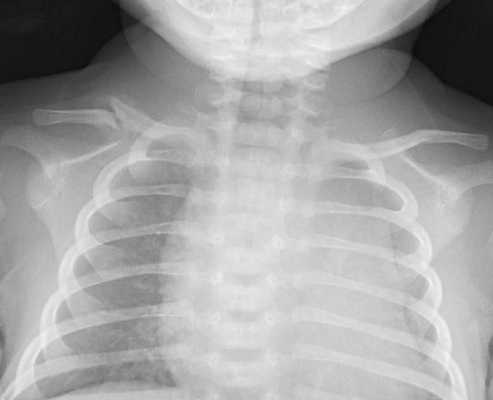

Правая голень Тани Л., 6 лет, была придавлена железобетонной балкой весом в несколько центнеров. Девочку освободили через 3—5 минут. При поступлении в больницу через 15 минут после травмы была в сознании, сонлива. На боли в правой ноге почти не жалуется. Бледна. Пульс 120 ударов в минуту, ритмичный, малый; дыхание частое и поверхностное. Органы брюшной полости безболезненны и не пальпируются, симптом Пастернацкого отрицателен. Правая голень бледно-синюшная, резко отечная, деревянистой плотности, на ощупь заметно холоднее левой, пульсация не определялась. На передней поверхности средней трети ее было видно синюшное углубление размером 5?2 см — след придавившего предмета. В последующие дни состояние продолжало оставаться тяжелым. Правая голень резко отечна, напряжена, болезненна, сине-багрового цвета. При рентгеновском исследовании определена трещина обеих костей правой голени в средней трети. На 3-й день отмечен положительный симптом Пастернацкого. Моча прозрачная, удельный вес 1010, следы белка, при микроскопии: лейкоциты — 10—15 в поле зрения, эритроциты свежие и выщелоченные — 15—20, гиалиновые цилиндры — 1—2. Общее количество мочи и остаточный азот крови не определялись. Таким образом, тяжесть состояния девочки и местные симптомы не могут быть объяснены наличием легкого травматического шока, отмеченного при поступлении, и трещиной костей голени. Это нашло отражение в клиническом диагнозе: синдром раздавливания, поднадкостничный перелом обеих костей правой голени на одном уровне, отечность деревянистой плотности правой голени. С 5—7-го дня началось постепенное улучшение, и через 29 дней больная была выписана для амбулаторного лечения. Через 4 года девочка здорова.